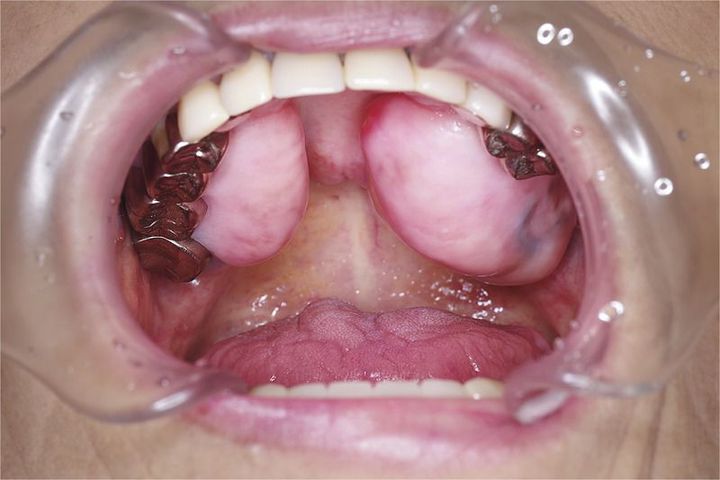

A 73-year-old woman presented with mouth dryness and tongue soreness. The oral cavity of the patient was dry, and Candida albicans was detected on culture. On examination of the upper jaw, firm protrusions of the alveolar bone were noted. Oral exostosis, a benign overgrowth of bone, was diagnosed. In this patient, oral exostosis had been present since childhood without any disturbance in her daily life and was an incidental finding. Her presenting symptoms were caused by a fungal infection and improved with treatment.